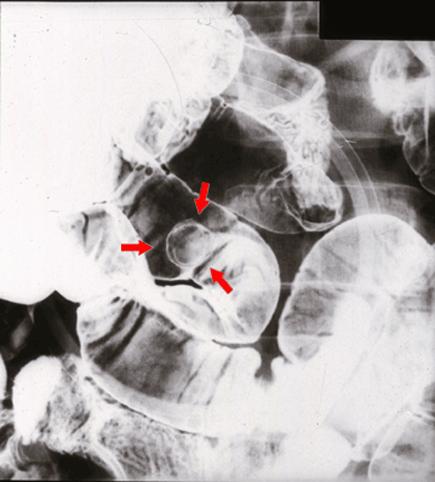

疾病(病理主体)的分类肿瘤样病变/其他

部位(按器官分)小肠/回肠

检查方法X线

肿瘤最大直径10~14

多发性肿瘤(同一器官)